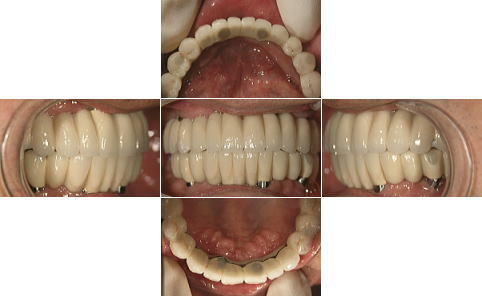

| 下顎の前歯部以外の全ての歯にグラツキがあったため、上顎はAll-on-4、下顎の奥歯は通常のインプラントブリッジとしました。 | |